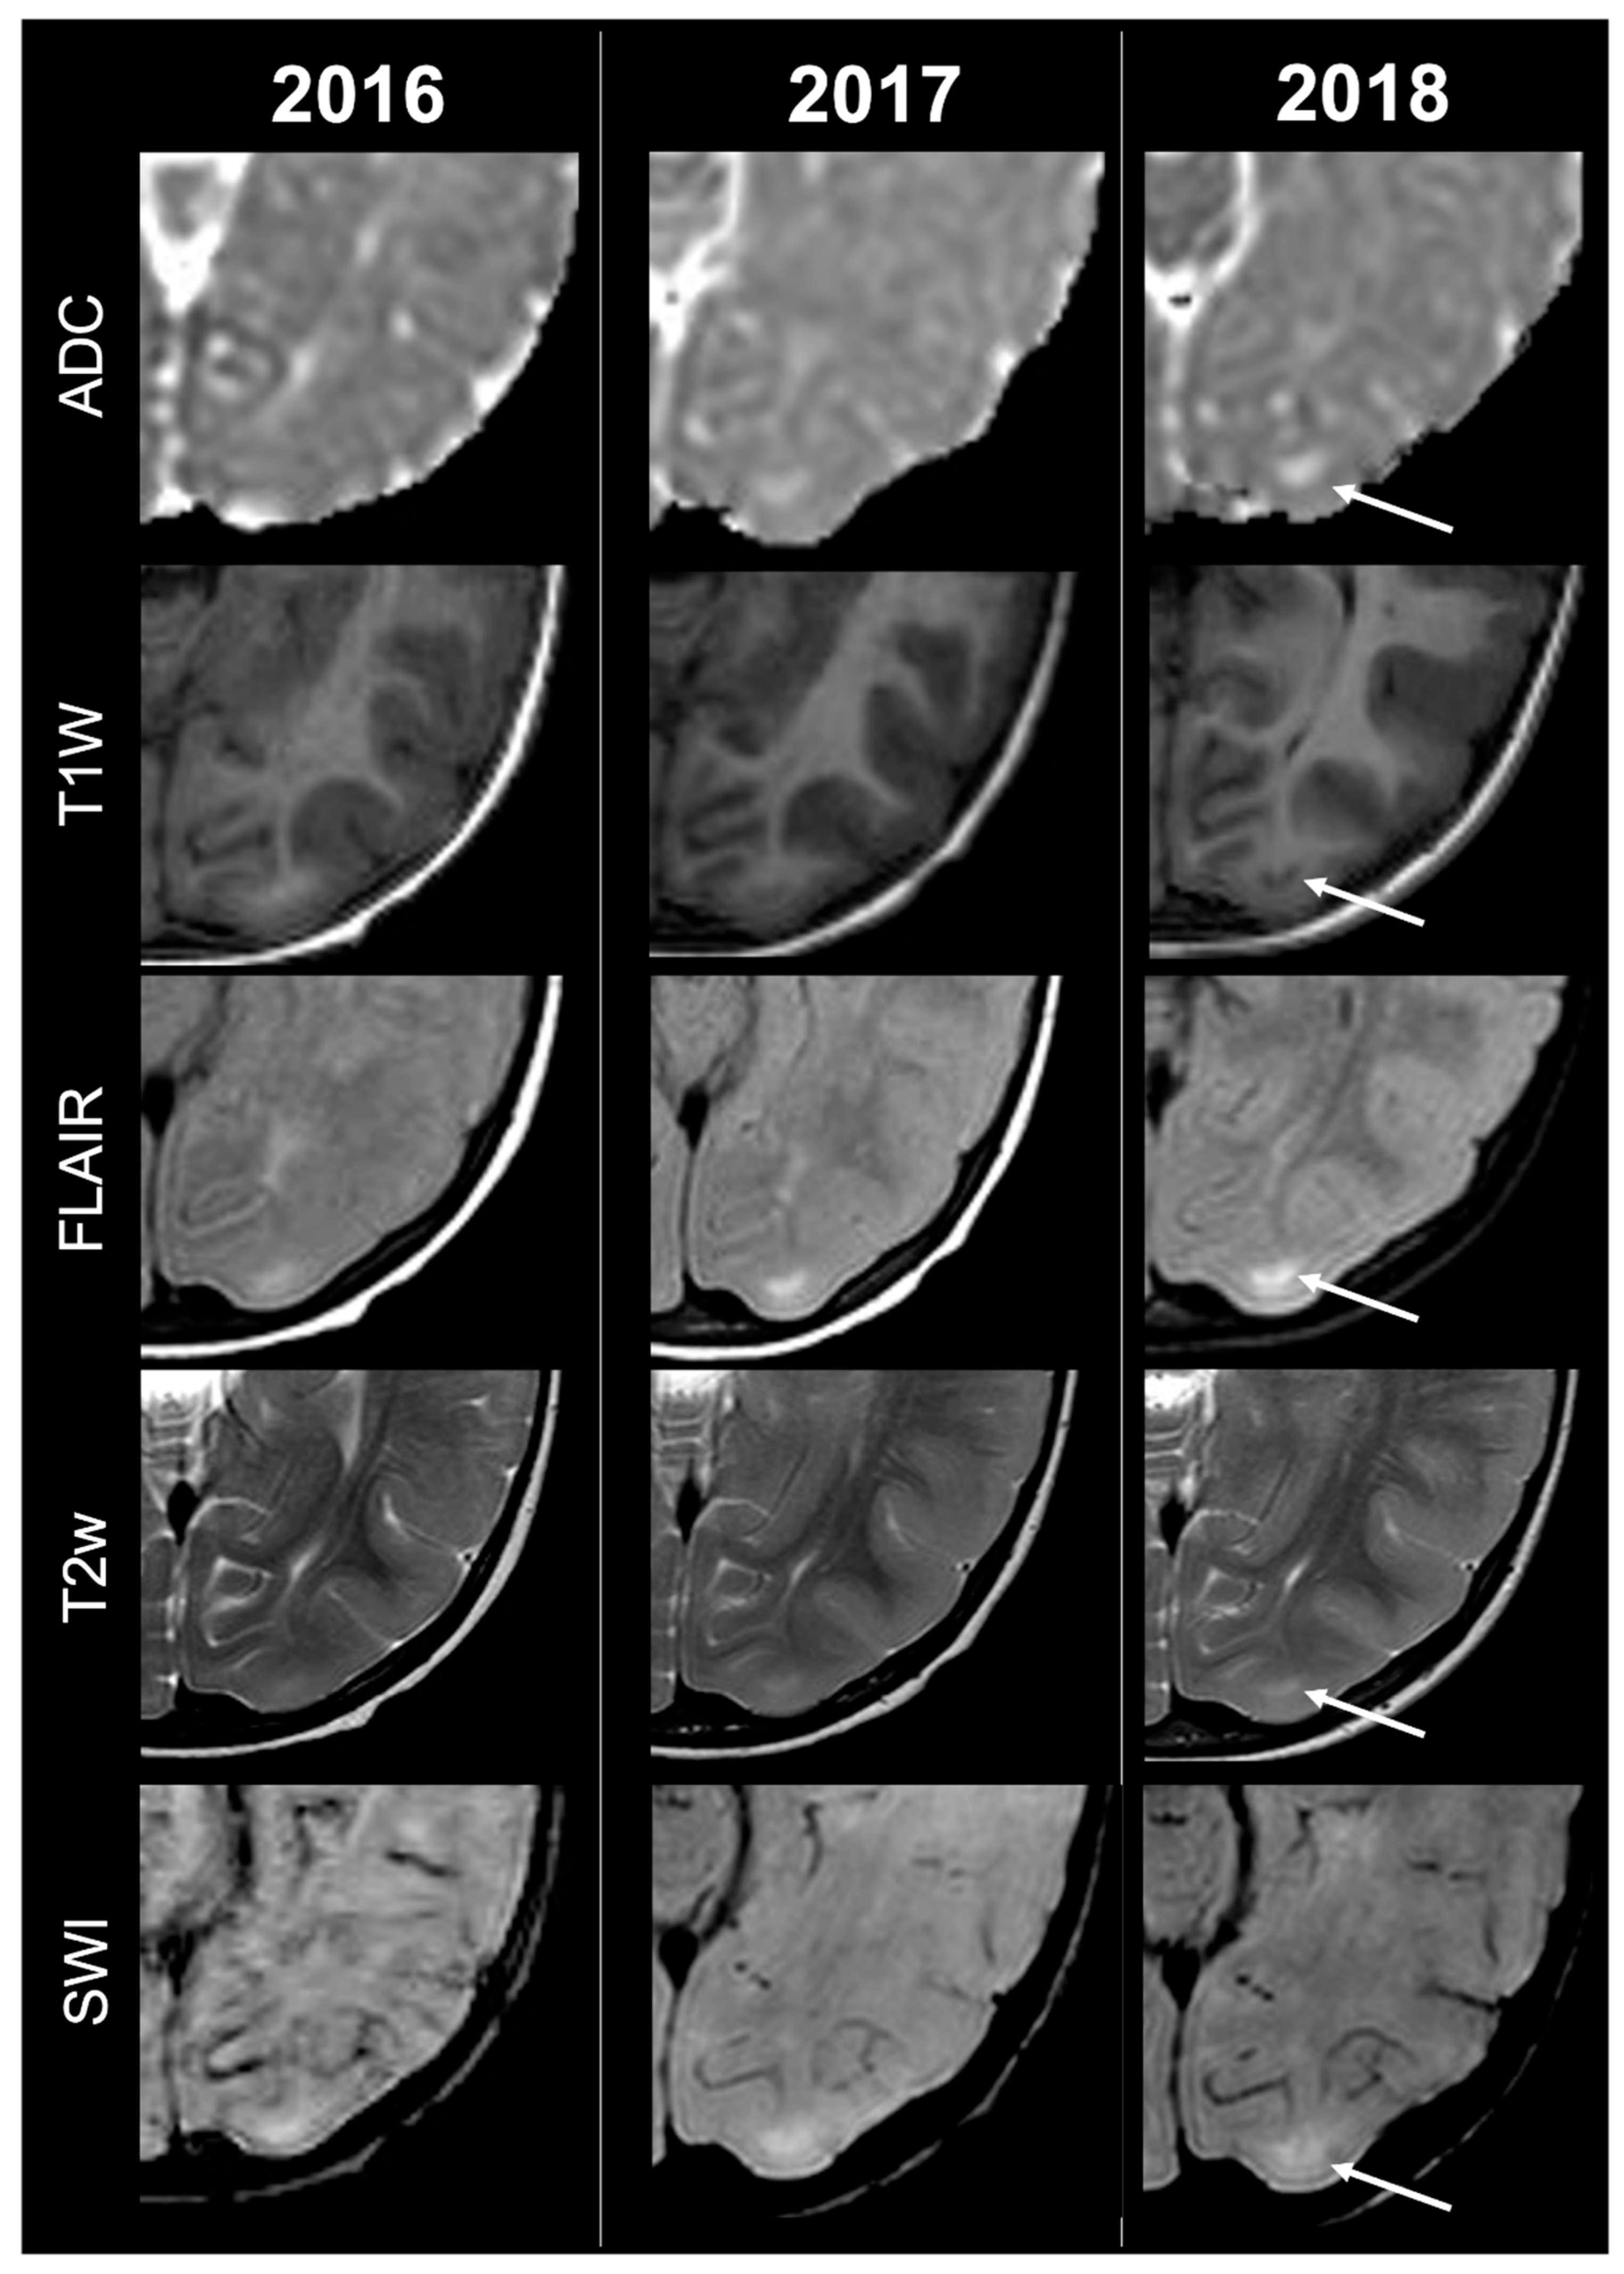

Concerning total lesion count, the interobserver agreement was excellent, with an ICC of 0.91 (95% CI: 0.87–0.95). At baseline, the total number of CTs identified across the cohort was 918 (mean ± SD = 16.1 ± 12.4), whereas at the last available MRI follow-up, the overall count increased to 1070 (mean ± SD = 18.8 ± 13.3), corresponding to a net gain of 152 CTs, equal to a relative variation of +17%. When stratified by tuber type, distinct trajectories were observed over time. Type A CTs, which were relatively abundant at diagnosis (N = 303, mean ± SD = 5.3 ± 7.0), decreased to 255 (mean ± SD = 4.5 ± 5.9) at follow-up, yielding a reduction of 48 lesions (−16%). Conversely, type B CTs showed an opposite trend, increasing from 438 (mean ± SD = 7.7 ± 8.4) at baseline to 556 (mean ± SD = 9.8 ± 8.6) at follow-up, corresponding to a net increase of 118 tubers (+27%). An example of MRI signal evolution from tuber A to tuber B is shown in Figure 1. Similarly, type C1 CTs rose from 160 (mean ± SD = 2.8 ± 4.8) to 220 (mean ± SD = 3.9 ± 5.8), with a net gain of 60 tubers (+38%). Type C2 CTs, initially rare at diagnosis (N = 14, mean ± SD = 0.2 ± 0.8), markedly expanded to 33 (mean ± SD = 0.6 ± 1.5), accounting for an increase of 19 CTs (+136%). Finally, type D CTs were only sporadically encountered, with a modest increase from 3 (mean ± SD = 0.1 ± 0.3) to 6 (mean ± SD = 0.1 ± 0.4), equating to a 100% variation. The observed increment of type C2 tubers was attributable almost exclusively to the progressive transformation of pre-existing type B lesions and, more prominently, type C1 lesions, while the increase in type C1 tubers reflected the gradual conversion of both type A and type B CTs that were already detectable at disease onset. An example of MRI signal evolution from tuber B to C1 is shown in Figure 2, while from tuber C1 to C2 in Figure 3. Only in one patient was a type C1 tuber newly identified at follow-up without clear evidence at baseline. In contrast, newly apparent tubers emerging over time but not clearly visible on baseline scans were most frequently represented by type A and type B lesions. Type D tubers were rare overall and were identified in only six lesions from four patients with a particularly high lesion burden; in all but one case they represented the evolution of type A or type B CTs (an example of MRI signal evolution from tuber A to tuber D is shown in Figure 4), while in a single case they were associated with adjacent subtle calcific foci. Overall descriptive data are summarized in Table 1.

Figure 3.

Left occipital tuber transition from type C1 to C2 at three different timepoints in a female patient diagnosed with TSC1.